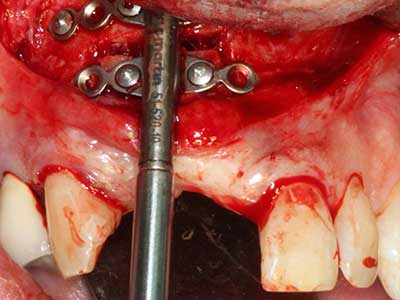

Sollen chirurgische Eingriffe mit unmittelbarer Knochenbeziehung an empfindlichen Strukturen wie Blutgefäßen oder Nerven erfolgen, so bergen rotierende Instrumente ein erhebliches Potential an iatrogener Schädigung. Gerade bei Nervdarstellungen nach iatrogener Schädigung, oder aber im Zuge einer Nervlateralisation für resektive und rekonstruktive Eingriffe oder Implantatinsertionen können piezoelektronische Geräte hilfreich sein Knochendeckel zu präparieren und nervnahe Hartgewebsanteile zu entfernen (Abb. 17-20). Ein leichter Kontakt des Nervstrangs zur Piezospitze bleibt dabei in der Regel folgenlos – allerdings kann eine unvorsichtige Vorgehensweise mit sägeartigen Bewegungen bzw. Ansätzen bei noch vorhandener knöcherner Unterlage durchaus temporäre oder aber auch permanente Nervschädigungen verursachen. Das Risiko einer solchen Schädigung wird jedoch als wesentliche geringer eingeschätzt als unter Anwendung von Säge- oder Fräsinstrumenten (Pereira, Gealh et al. 2014).

Abb. 18: Präparation eines Kortikalis-Deckels mit der Piezo-Knochensäge (Piezomed, W&H).

Abb. 19: Operationssitus nach Neurolyse und Osteomentfernung.